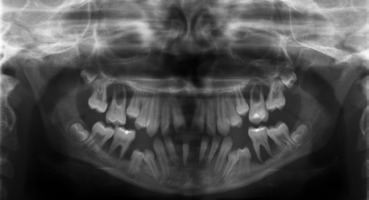

When the patient was 10, the exposure of two-thirds of palatal roots and third-degree loosening of teeth were observed (Fig. 3). A panoramic radiograph picture was taken (Fig. 4), which revealed complete absence of the bone base in all permanent first molars. Teeth 16 and 26 were qualified for extraction, which was performed in an outpatient setting under local anesthesia and antibiotic treatment (clindamycin, 10 mg/kg/dose). The obtained material from granulomatous lesions was submitted for histopathological examination, the results of which indicated non-specific inflammatory granulation tissue.